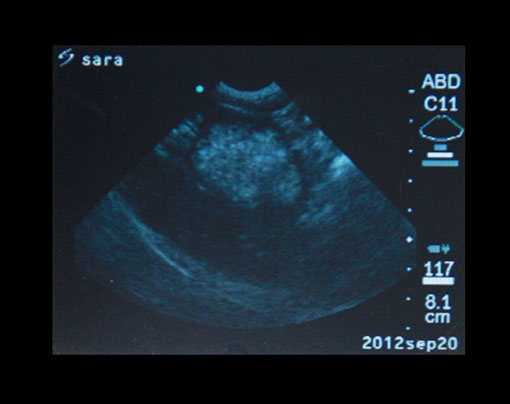

ecografía

Cada vez más, la ecografía, es utilizada en la medicina veterinaria, con esta podemos diagnosticar diversas patologías de órganos internos.